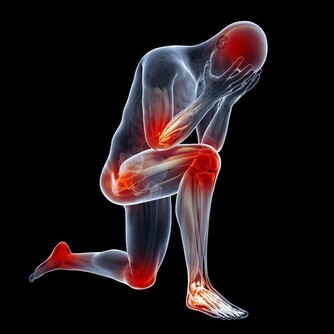

1. 腿部腫脹疼痛

如果血栓源於腿部,當它形成時,靜脈中會出現腫脹,這會導緻小腿肌肉疼痛。更糟糕的是,小腿組織很厚,因此身體系統難以消除血栓。所以,如果你發現自己吃了消腫藥卻不起作用,那就說明可能存在血栓。

8. 經常腿抽筋

每個人都會時不時抽筋,但你要知道,與凝血有關的脫水也能導致肌肉痙攣。所以,如果小腿抽筋變得頻繁,這是一個嚴重的跡象,表明可能存在血栓。通常,緩解痙攣的方法是向後彎曲足部以拉伸肌肉。如果這種做法沒有幫助,並且疼痛增加,原因很可能就是血栓。

9. 腳和小腿疼痛

小腿上的深靜脈血栓,會造成嚴重的疼痛,使人步行困難並且坐著也會疼。不僅如此,腳部疼痛也是其後果之一,由於血栓妨礙血液流向足部,導致足部缺氧,造成嚴重不適。